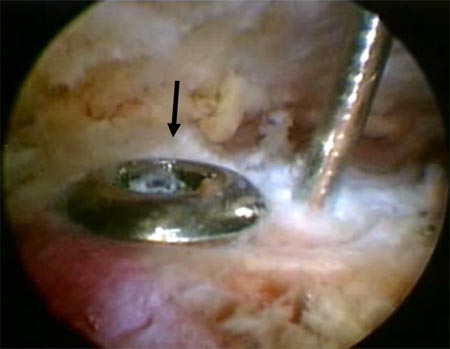

Si la reducción de los fragmentos es correcta en las imágenes por radioscopía, la fijación temporal de los fragmentos óseos con clavijas percutáneas es llevada a cabo. Posteriormente y según el tamaño de los fragmentos se utilizan tornillos canulados de 2.7 mm, 3,5 mm y/o 4.5 mm. Es importante remarcar nuevamente la no resección de los tejidos blandos (manguito rotador) de los fragmentos óseos. En 4casos de fracturas conminutas la reducción y osteosíntesis de los fragmentos fue lograda a través de los tejidos blandos y no del propio tejido óseo. Si la reducción de los fragmentos no es correcta la inspección del lecho de la fractura, primero a nivel articular y luego a nivel subacromial, es llevada a cabo con el fin de facilitar la misma mediante la remoción de tejidos interpuestos. En todos nuestros pacientes fueron colocados no menos de 3 tornillos de fijación (Fig. 1 y 2).

Figura 2D: Flecha negra: Clavija percutanea mantiene la reducción. Flecha Amarilla: línea de fractura./ Figura 2E: Osteosíntesis con tornillo canulado de 3.5 mm./ Figura 2F: Resultado. Escalón superior de 2 mm. Reparación de Bankart y SLAP.